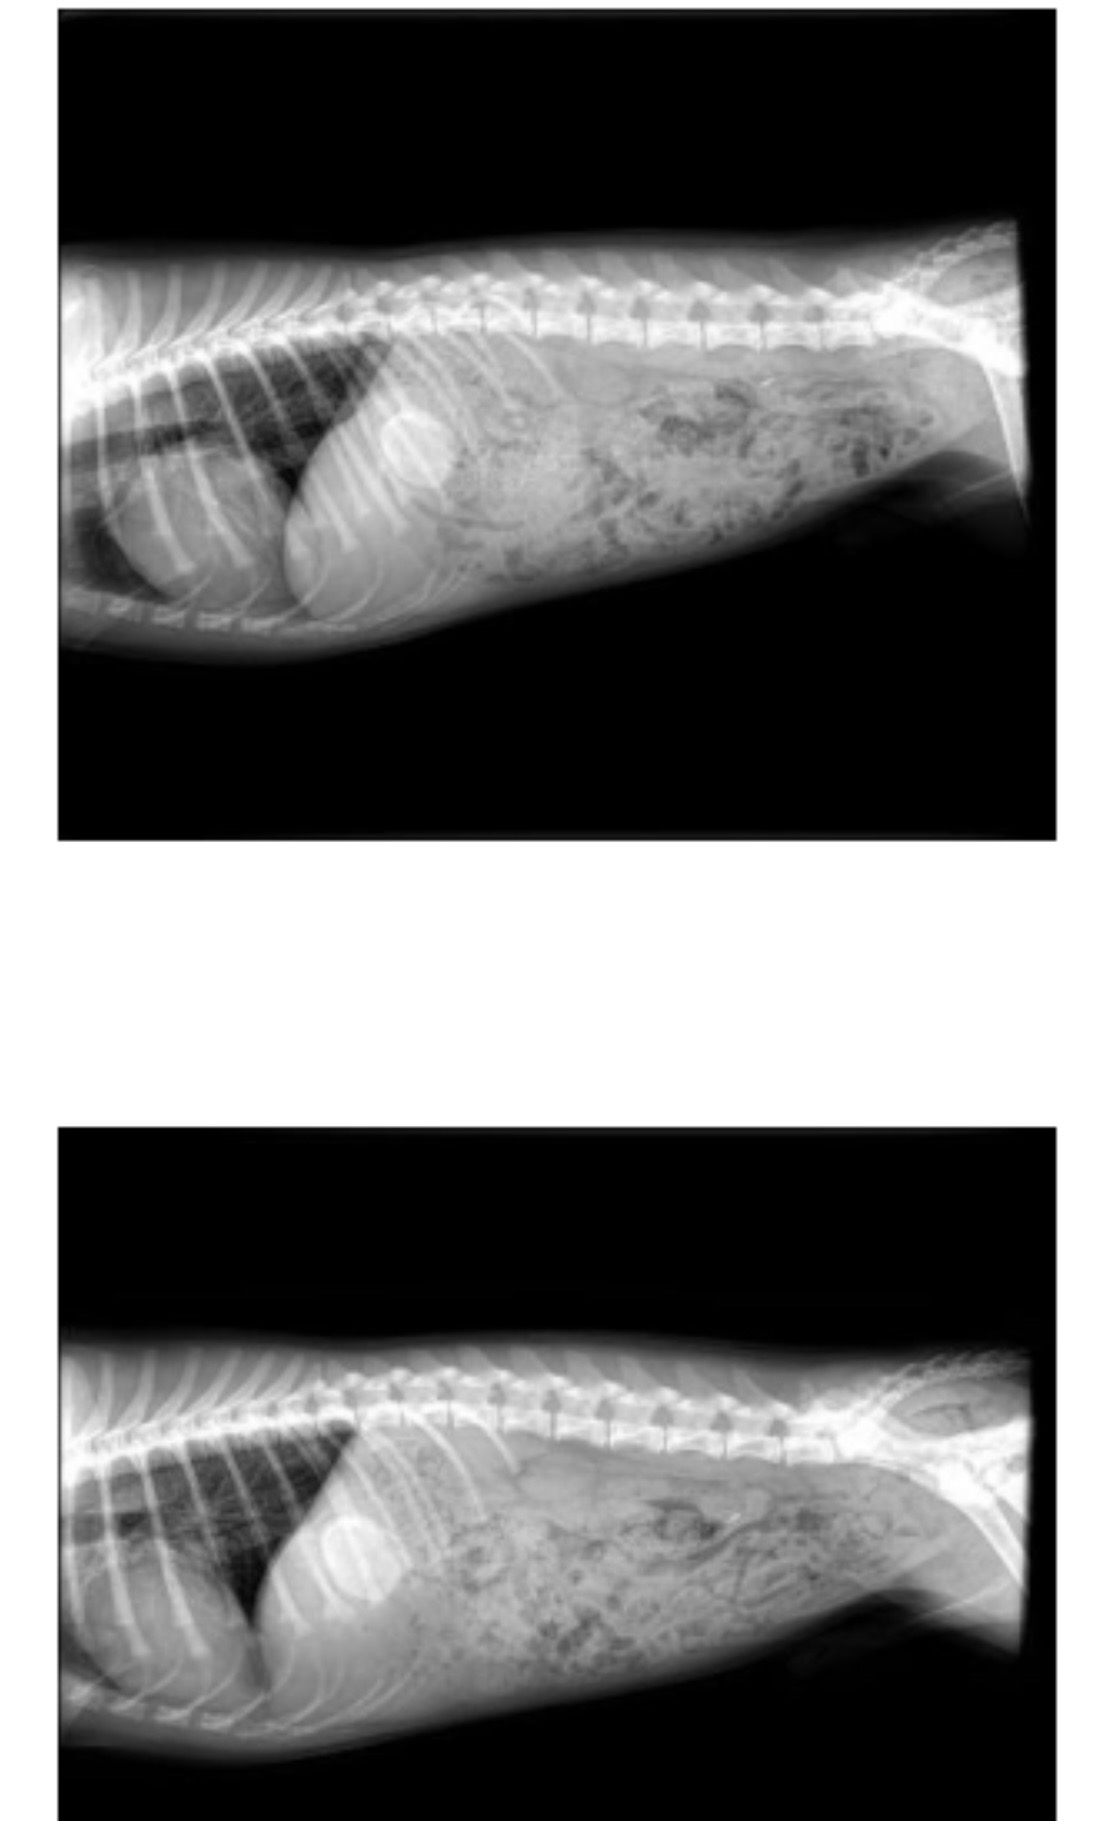

A few months ago, we noticed a small lump on his side. As time went on, it continued to grow. On Valentine’s Day, my aunt took Mango in for X-rays, hoping for simple answers. Instead, she was told he has a mass on his 10th rib that has been there since birth and has progressively gotten larger.

Right now, the vets don’t know if the mass is malignant or benign. To find out, Mango needs a biopsy that costs $3,000. No matter the results, the mass must be surgically removed to prevent it from affecting his quality of life or potentially becoming cancerous. The surgery is estimated to cost upwards of $7,000.